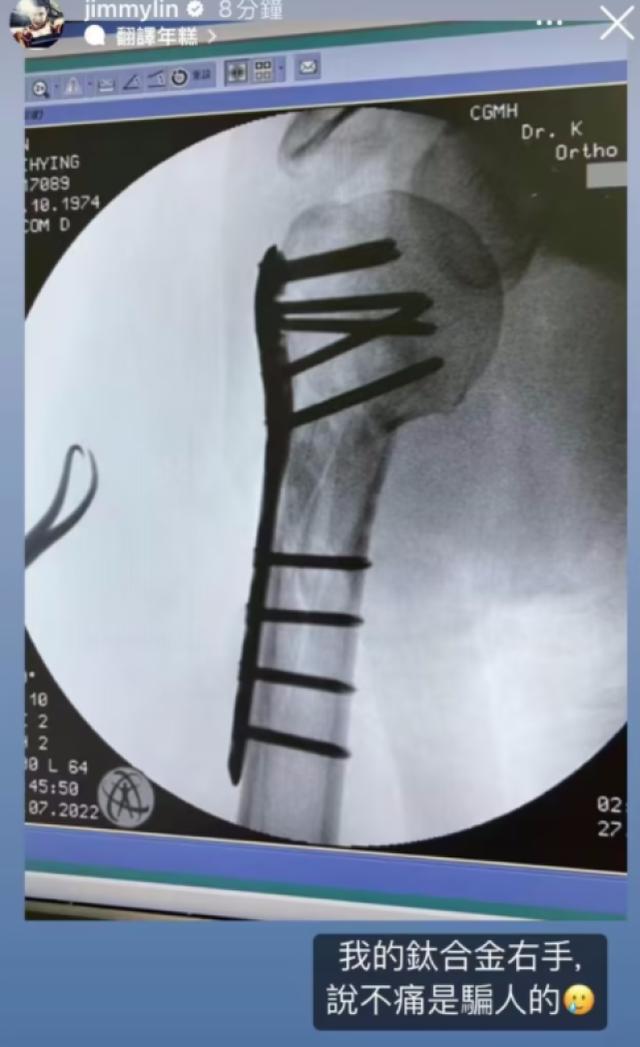

与此同时,林志颖还首度公开了自己受伤右手的X光片,因为右手骨折林志颖在接受手术时直接打入了十一颗钢钉。现在的林志颖看起来充满元气,但实际上他一直承受着巨大疼痛,林志颖写道:“我的钛合金右手,说不痛骗人的”。